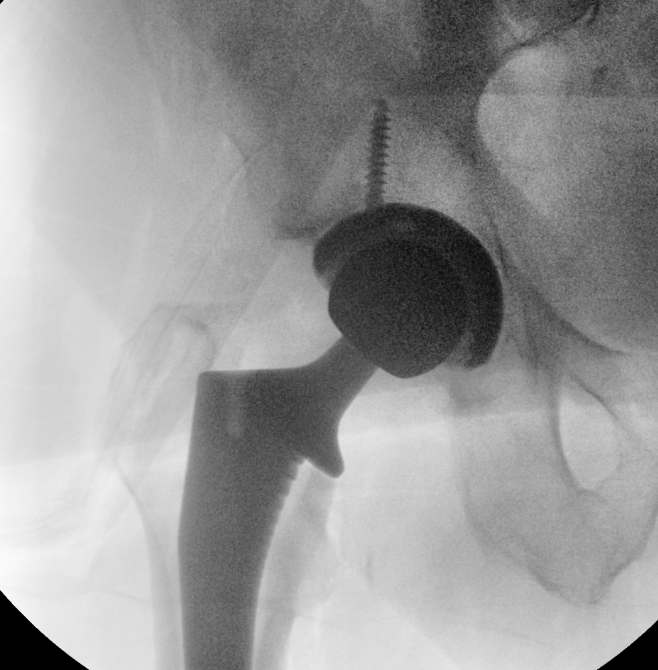

Intra-operative fluoroscopy

Advantage

- assesses femoral fit and fill

Issues

- 2 dimensional image

- easier in supine position / direct anterior THA

- parallax and distortion

- less accurate for acetabular anteversion